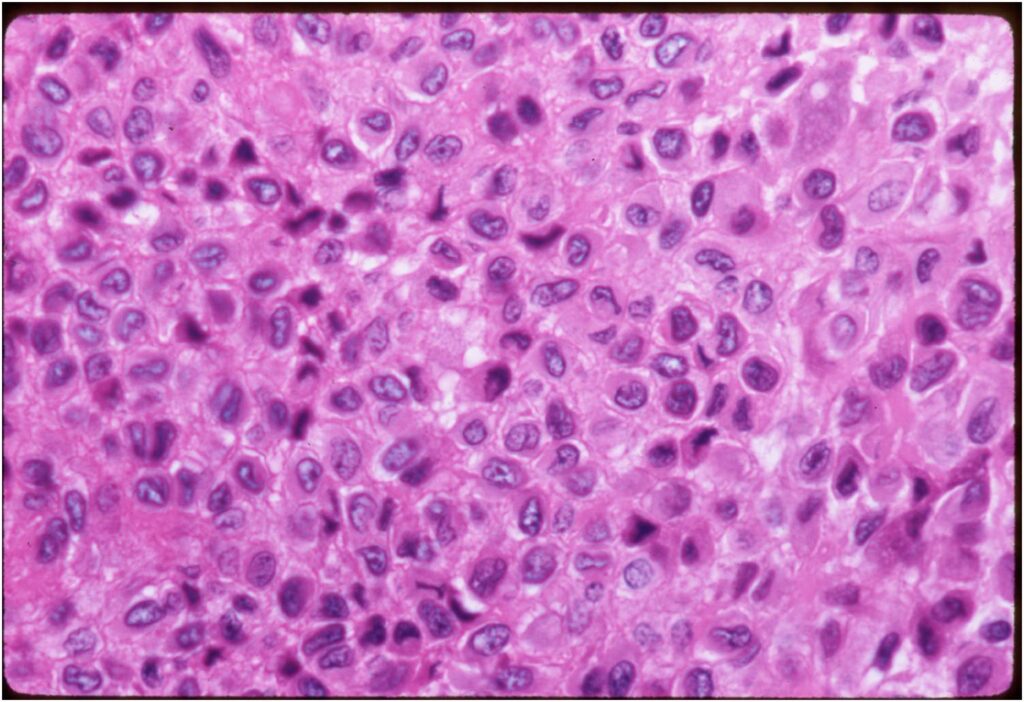

- The tumor is composed of chondroblasts that have a distinct, thick cell membrane. The thick cell membrane gives it a “Chicken Wire Fence Appearance,” especially when the cell membranes are calcified